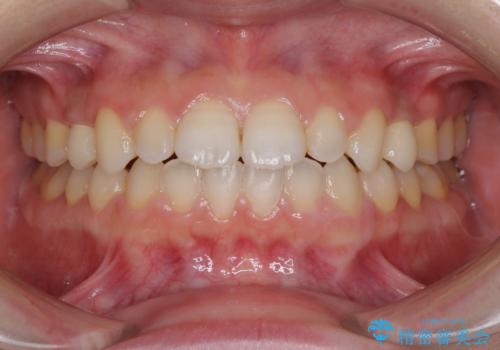

治療の期間と費用はかかりますが、初診時とは比べものにならないほど良好な状態にて治療を終えることができました。